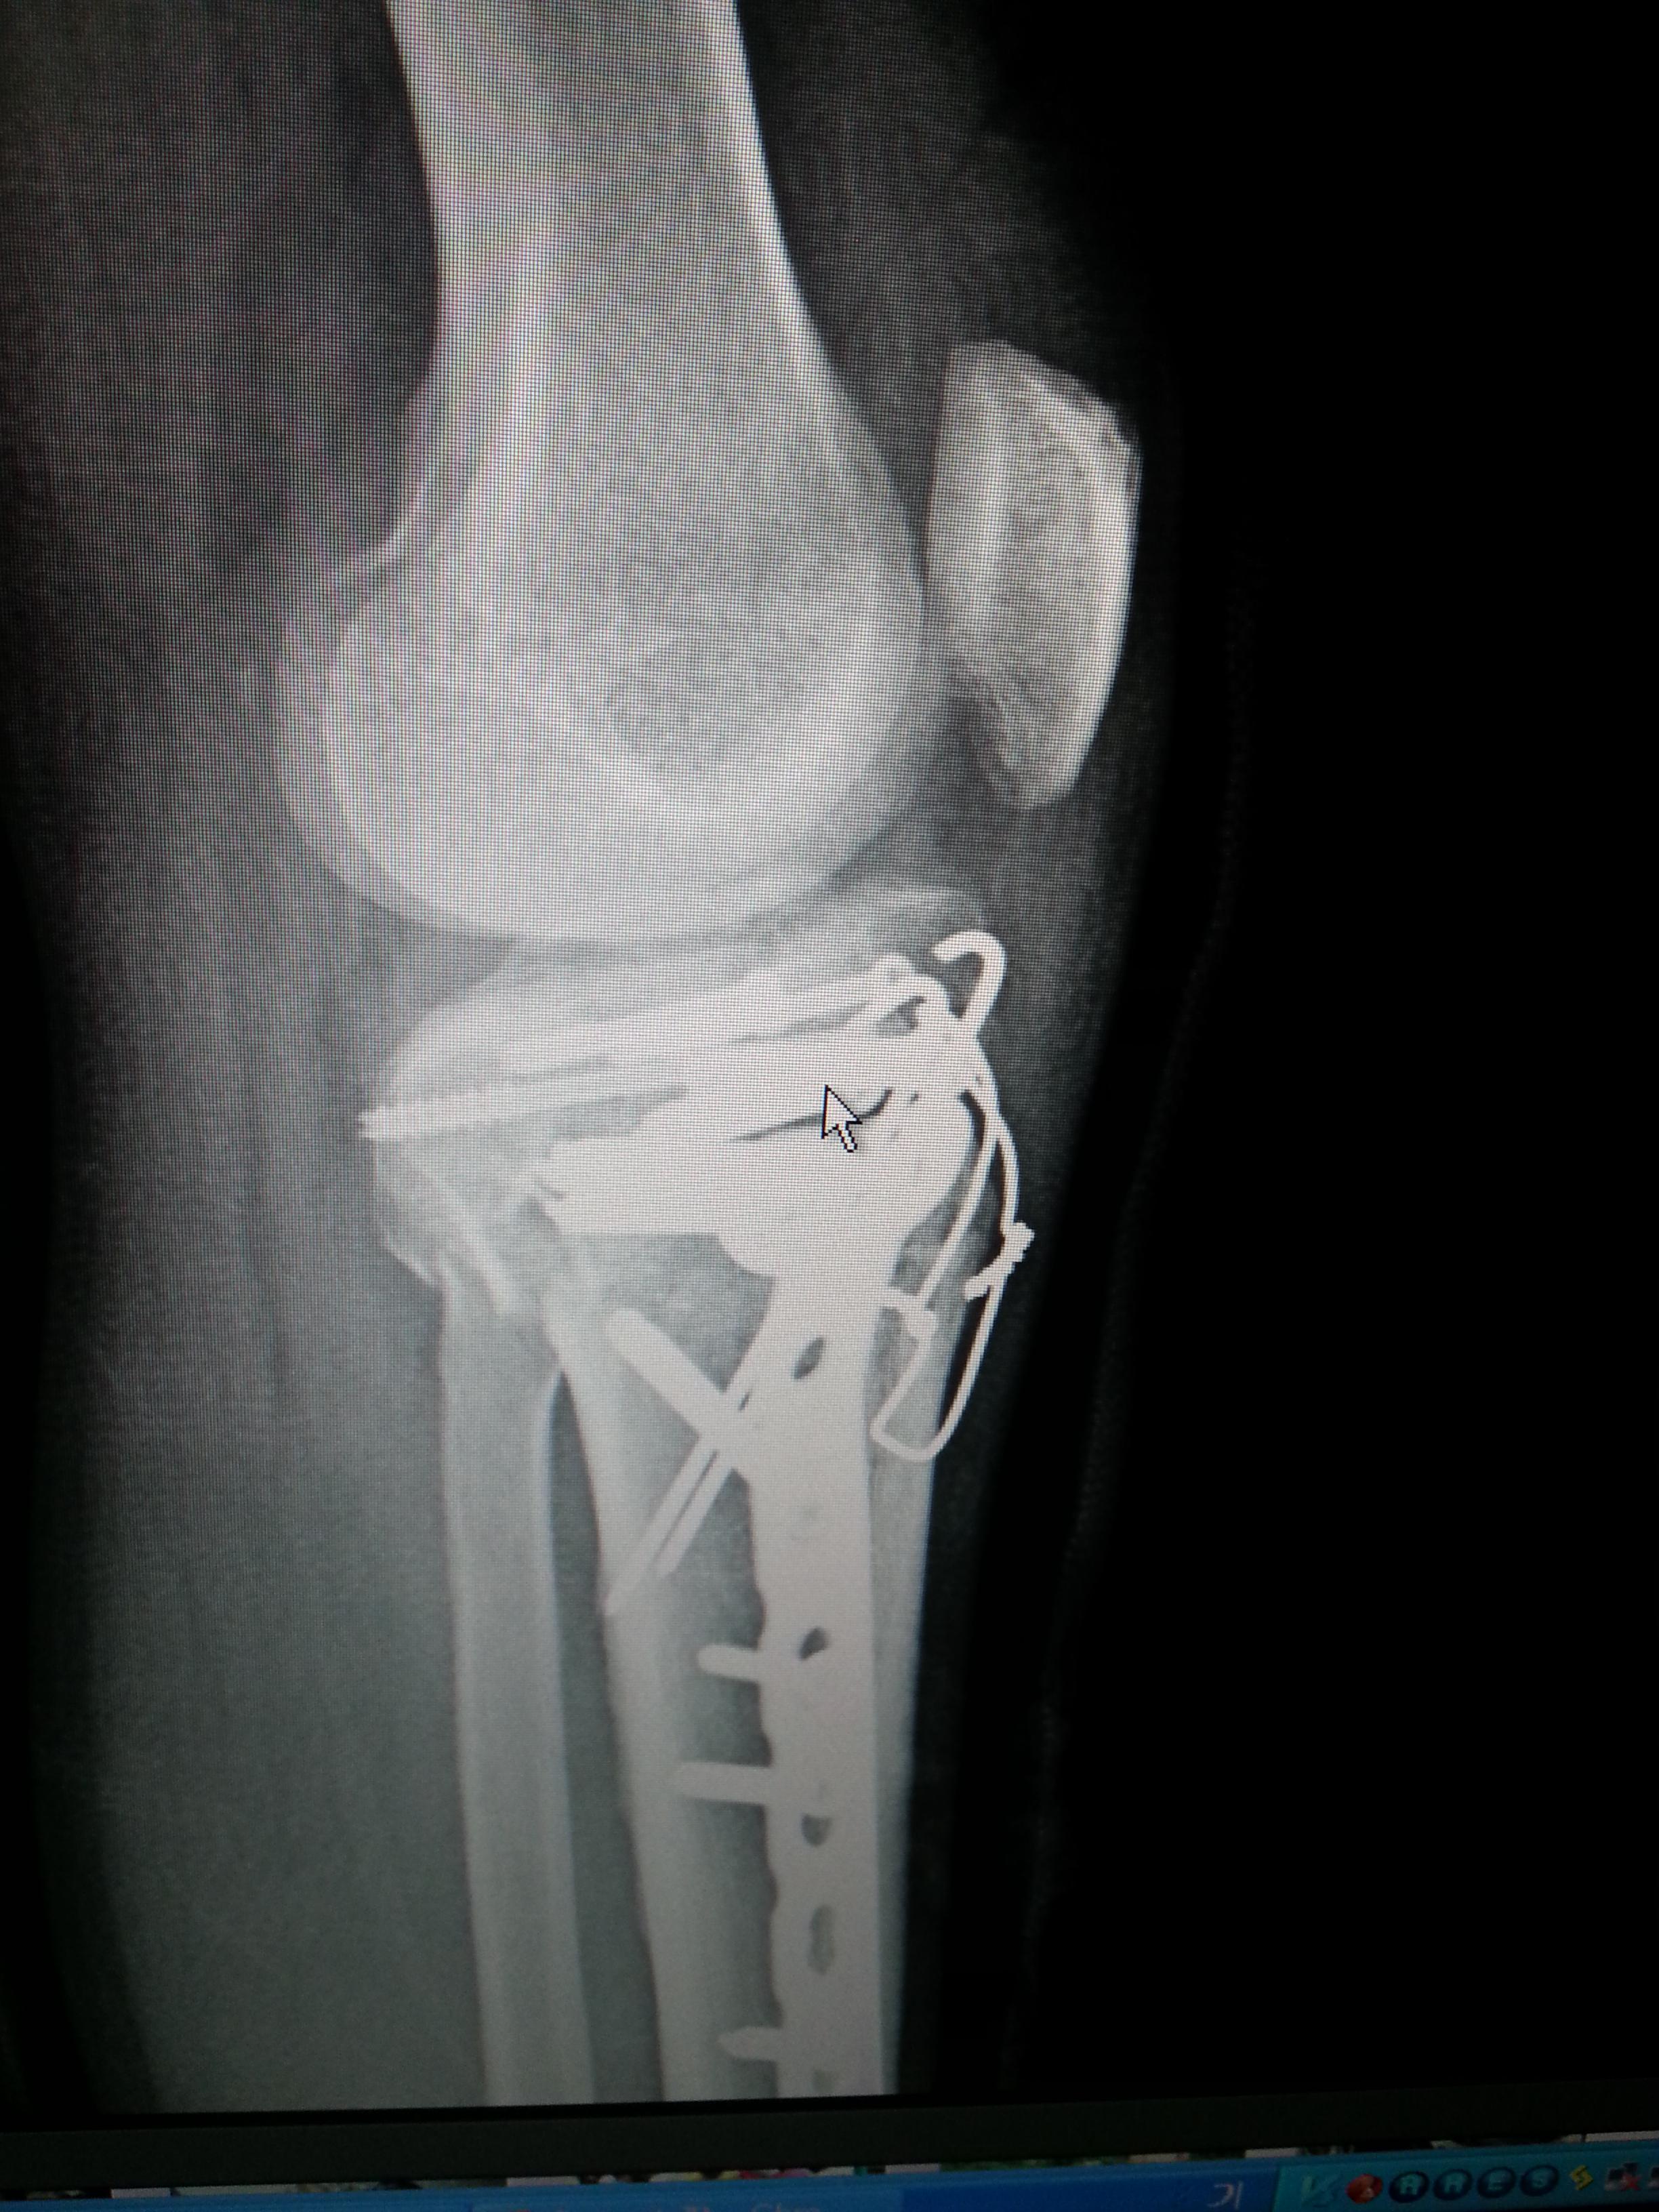

오토바이를 타고 가는데...배달하는 어린 아이가 나를 들이 받아서...

나는 그날 이후로 장애인이 되어 버렸다..

주요한건..오늘자..아직도 이 핀을 제거하지 못하고..

아직 정상적인 상태가 아니란것...